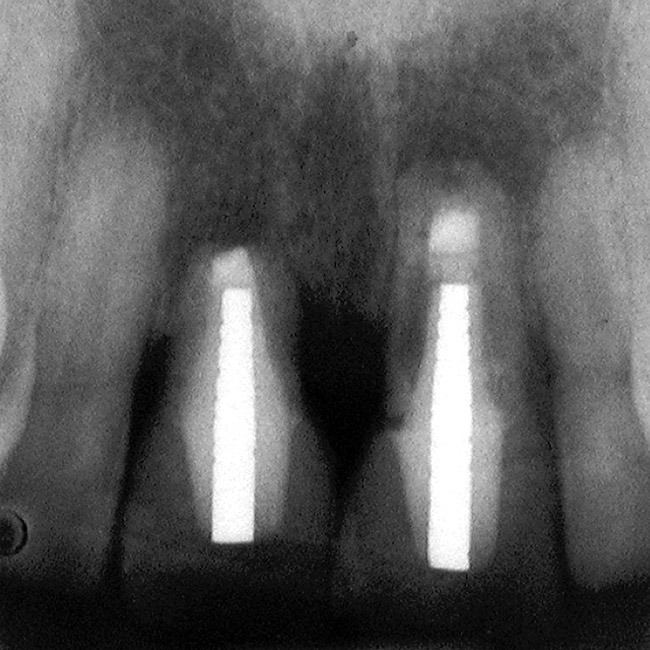

Figure 6  Excellent interproximal crestal bone level between the centrals before extraction.

Figure 6

Figure 15  Excellent bone levels.

Figure 15